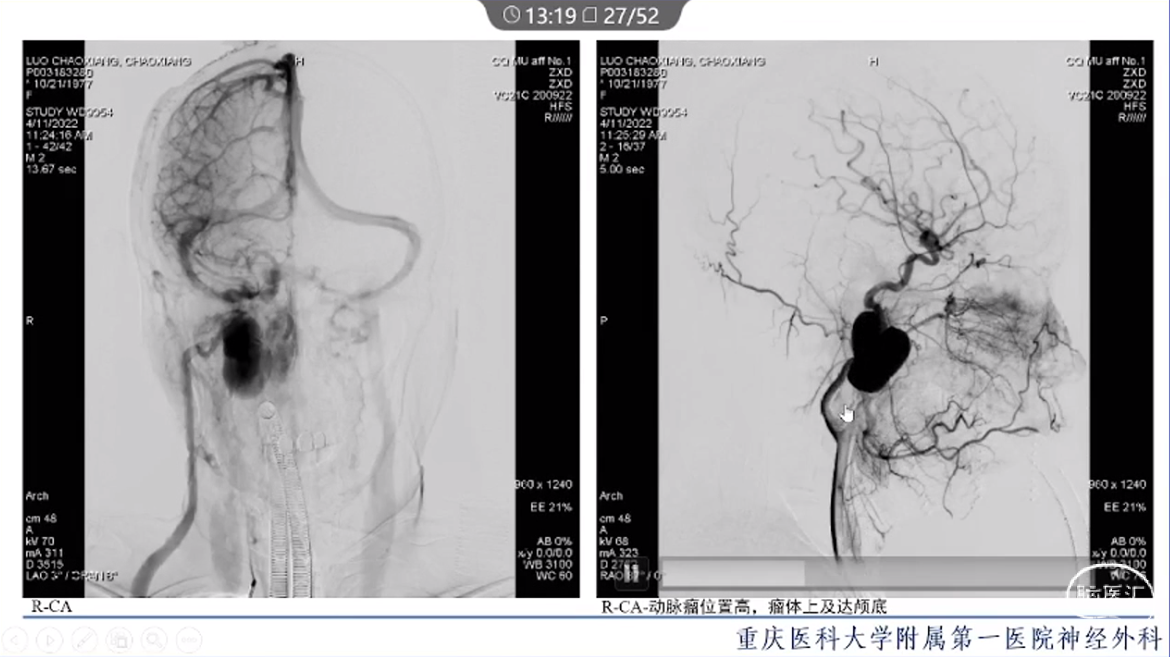

·颈内动脉颈段动脉瘤治疗方式有血管内治疗、外科手术和保守治疗。

·血管内治疗是最常见的治疗方式,随着血管内介入技术的发展和材料的进步,越来越多的动脉瘤可以通过血管内途径治疗。

·对于血管扭曲、血管直径大以及存在抗血小板禁忌的动脉瘤患者,特别是对于颈段大型或巨大型动脉瘤的治疗,常需要外科手术治疗。